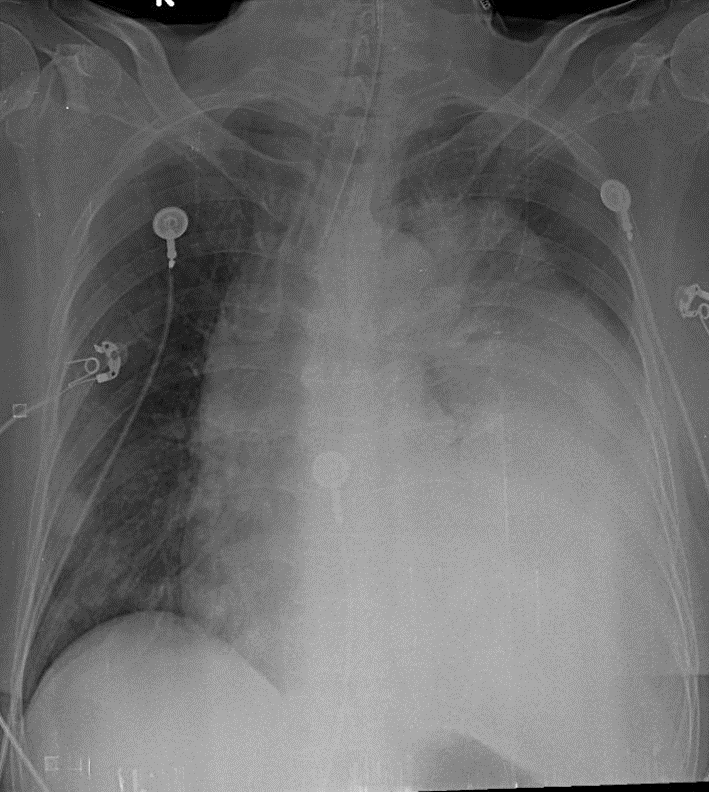

1-Khí quản lệch(P) 2-Đang đặc nội khí quản 3-U thùy dưới phổi (T) 4-Nhiều tổn thương dạng nốt nhỏ rải rác phổi (P) => Di căn